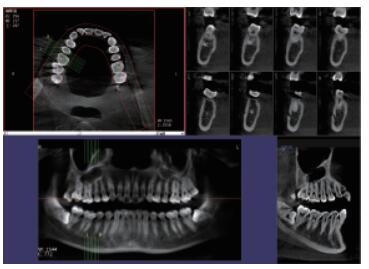

高清晰成像口腔CBCT 牙科CT產(chǎn)品說明:

你知道口腔CBCT是什么意思嗎?口腔CBCT是一類特殊的CT,其工作原理是通過X線發(fā)生器以較低的射線量發(fā)射錐形X束,圍繞投照體做環(huán)形數(shù)字式投照,將圍繞投照體多次產(chǎn)生的二維投射影像通過圖像重建算法獲得三維圖像。成像效果更好,有助于醫(yī)生的診斷,對于種植、綜合診斷、正畸等牙科診斷均有較大幫助。

在口腔影像等細(xì)分領(lǐng)域,口腔CBCT的成像質(zhì)量優(yōu)于CT和普放。CBCT的X線利用率更高,且生成的圖像具備很高的各項(xiàng)同性空間分辨率。CBCT技術(shù)優(yōu)勢如下:

口腔CBCT設(shè)備大大提高了口腔科準(zhǔn)確化醫(yī)療和臨床水平。以南京普愛醫(yī)療口腔CBCT為例,其肩負(fù)著臨床七大學(xué)科疾病的診斷需求:種植、正畸、牙體牙髓、牙周、顳下頜關(guān)節(jié)、頜面外科和其他,以掃描速度快、成像速度快、圖像質(zhì)量高、視野大、操作軟件專業(yè)性強(qiáng)等優(yōu)點(diǎn),輔助各種臨床診斷與治療、術(shù)前檢查及針對性治療方案。普愛醫(yī)療口腔CBCT產(chǎn)品特點(diǎn):

三維重建任意斷層

專有三維重建算法,可提供任意位置高清斷層影像。

高清口腔全景影像

通過三維容積影像,提取高清口腔全景影像。

多平面組合重建

可同時(shí)觀察軸向面、冠狀面和矢狀面圖像,方便臨床診斷。